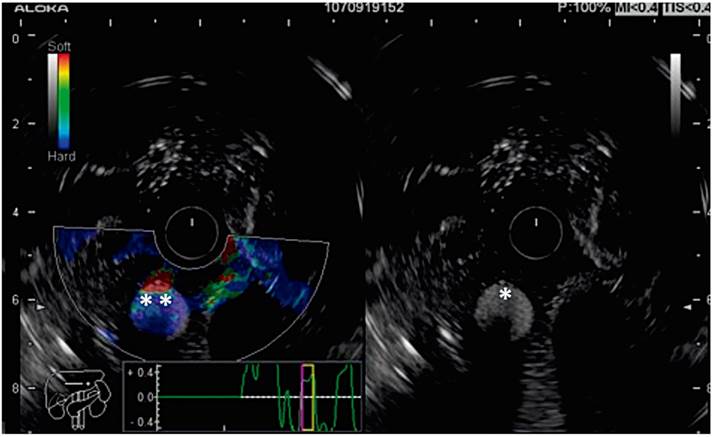

Figure 7 Elastography model and echoendoscopic view. Note the different echogenic characteristics of the cystic and solid lesions on the right. On the left, the cystic lesions have no elastographic pattern (*).

Next, students investigate characteristics of the lesions (previously introduced objects) that they identify and learn about echogenic image qualities from anechoic indicating liquid, through isoechoic, hypoechoic and hyperechoic.